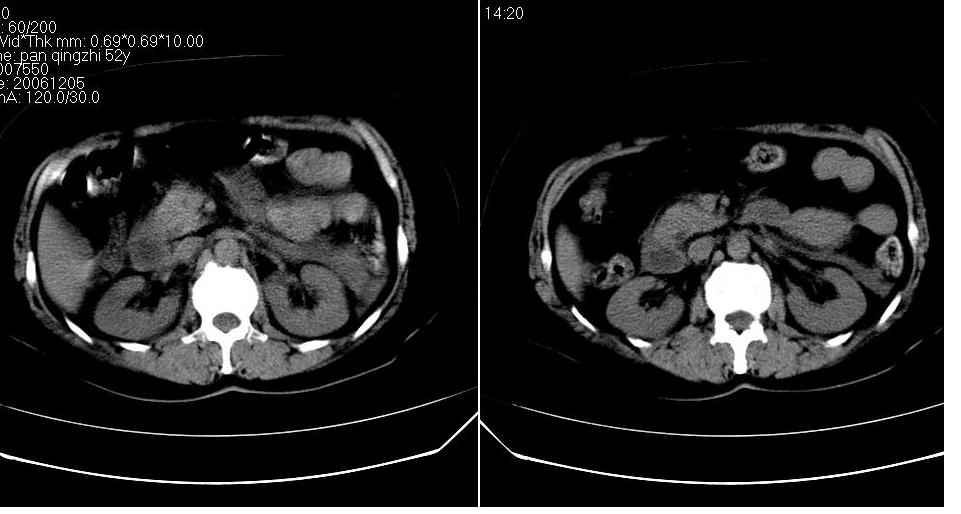

女 52岁,腹痛两天,无其它不适。

左肾周筋膜增厚,肾前间隙积液,胰腺肿大,胆囊结石,胰腺炎

胆囊结石 胰腺炎伴胰尾假性囊肿形成.

胆囊结石,胆总管结石.胰腺炎,胰尾假囊肿形成.

胰头部囊状影是十二指肠。左侧肾前筋膜增厚、少量积液,胰腺增大,边缘模糊,支持胰腺炎。

2、胆源性胰腺炎,诊断依据:同1外+左肾周筋膜增厚,肾前间隙积液,胰腺肿大。

持:左肾周筋膜增厚,肾前间隙积液,胰腺肿大,胆囊结石,胰腺炎。